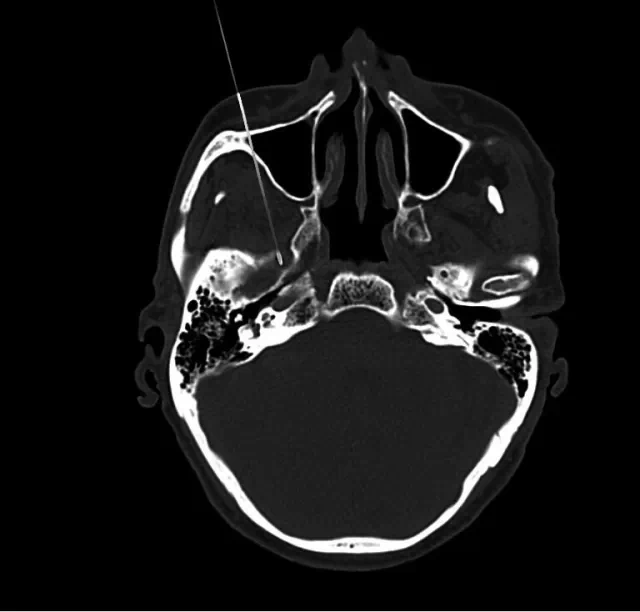

(二)四川奥斯迪康骨医院治疗方法:CT引导射频热凝术

治疗原理:三叉神经为感觉神经,其中神经纤维(AA纤维和AB纤维)能耐受较高温度,而痛觉神经纤维不能耐高温,CT引导三叉神经热凝术选择破坏痛觉纤维,使患者疼痛治愈。